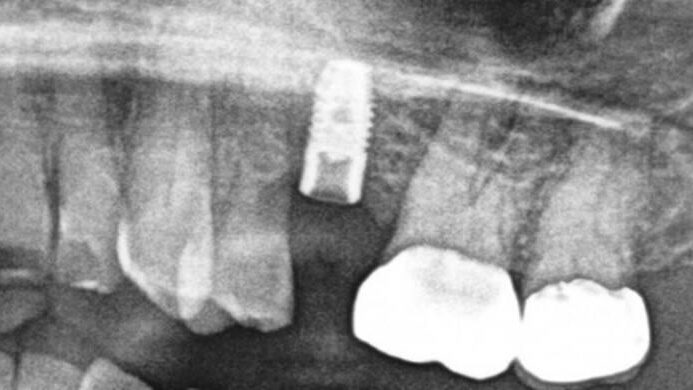

A Type V Abutment and Abutment Screw Recovery Case created by Prior Eccentric Free Hand Drilling – 0041

This case showcases an example of A Type V Abutment and Abutment Screw Recovery Case created by Prior Eccentric Free Hand Drilling.

A Diagnostic and Treatment Algorithm for Fractured Implant Screw Retrieval: Organizing for a Safe Recovery to Preserve Implant Integrity.

This implant case exemplifies a Failed Fractured Abutment Screw Recovery attempt with a Salvin screw recovery kit.